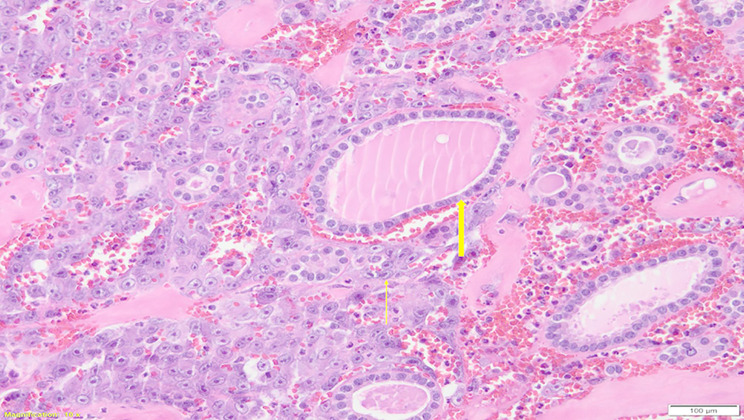

Background: Thyroid angiosarcoma is a rare, highly aggressive malignancy of endothelial origin, characterized by rapid growth, invasive behavior, and a high metastatic potential. While most cases are reported from the Alpine regions of Europe, its occurrence elsewhere is exceedingly rare. The aim of our review is to report a case of thyroid angiosarcoma and provide a systematic review of the literature, focusing on clinical presentation, diagnostic strategies, and treatment outcomes.

Results: A systematic review of 72 cases of thyroid angiosarcoma reported in 52 articles was conducted. The median patient age was 66 years, with female predominance (4:3). Most patients presented with a rapidly enlarging thyroid mass and compressive symptoms. Diagnosis required a combination of histopathology and radiologic imaging, with Fine Needle Aspiration Cytology as the initial tool in 47% of patients. Total thyroidectomy was performed in 67% of cases, and 42% of patients received adjuvant therapies. The prognosis remains poor, with a median overall survival of 28 months and a 3-year survival rate of 40%.